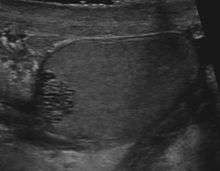

Tubular ectasia of the rete testis

Rete tubular ectasia is a benign condition, usually found in older men, involving numerous small, tubular cystic structures within the rete testis.

The condition can be detected with sonography. It is commonly associated with epididymal abnormalities, such as spermatocele, epididymal cyst, and epididymitis. The condition shares a common location with cystic dysplasia of the testis and intratesticular cysts. Unlike cystic neoplasms, they don't present specific tumor markers.[2]